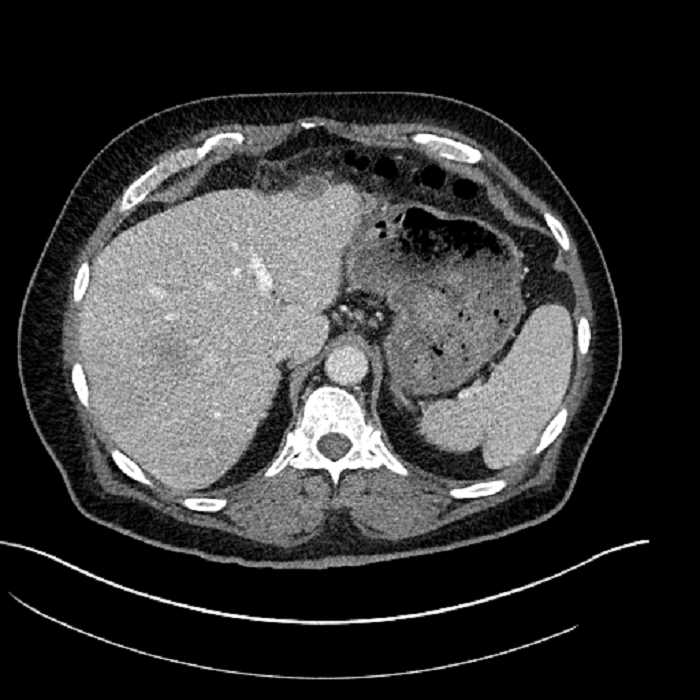

Age: 63

Sex: Male

Indication: Abdominal pain

• Large fluid density structure in hepatic segments 7 and 8 measuring 10 x 7 x 7 cm with internal septation and circumferential ill-defined low density compatible with edema

• Peripherally enhancing subcapsular collections along the anterior margin of the left hepatic lobe measuring 3 x 1 cm and 2 x 1 cm

• Clearly marginated fluid density structure in segment 7 and several other scattered tiny hypodensities, which likely represent cysts

• Hepatic abscess

Acute sigmoid diverticulitis complicated by a small contained perforation and a large abscess in the right hepatic lobe. Additional small subcapsular abscesses along the anterior margin of the left hepatic lobe.

• The classic CT imaging appearance is a double target sign with internal low density surrounded by an internal enhancing rim (capsule) and a low density external rim (edema)

Hepatic abscess showing the double target sign with low density internally surrounded by a thin inner enhancing rim (red arrow) and ill-defined outer low density rim (yellow arrow). Blue arrow indicates an internal septation. Red arrows: additional smaller subcapsular abscesses. Red arrow: focal contained perforation associated with diverticulitis.